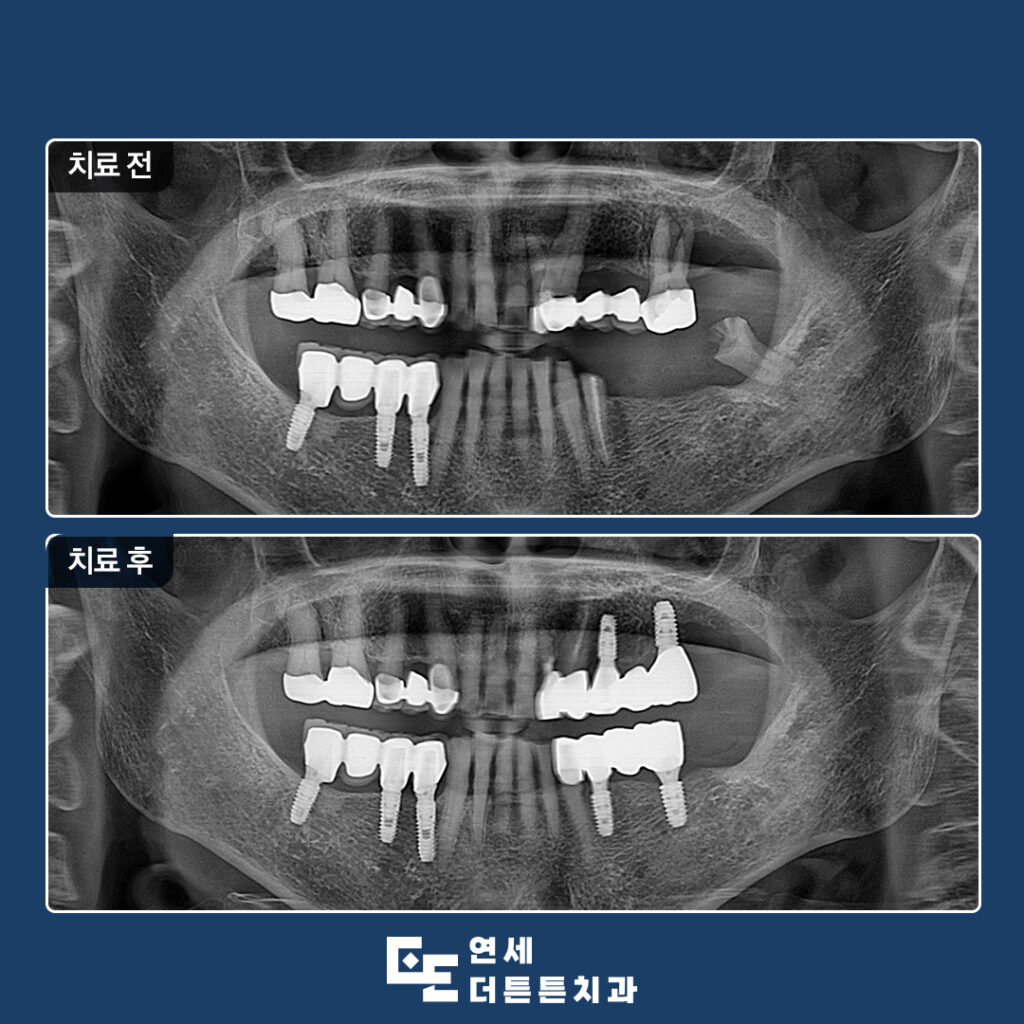

오늘은 망가진 어금니 기능 회복을 위해 임플란트를 진행하신 환자분을 소개해 드리도록 하겠습니다.

환자분께서는 왼쪽 아래 어금니가 다 빠져버리고 오른쪽으로만 식사를 하시다보니 불편하여 치료 상담을 위해 도봉동치과에 내원해 주셨는데요. 왼쪽 위에는 오래된 브릿지가 있었고 아래쪽은 상실한지 오래 되어 기능을 못하고 있는 상태로 위쪽의 브릿지를 제거하고 위, 아래 임플란트를 진행하시기로 계획을 수립하였습니다.

예후가 좋지 않은 치아는 발치 후 임플란트 식립, 살려쓸 수 있는 치아는 신경치료 후 크라운 수복으로 치료를 문제 없이 마무리하였습니다.